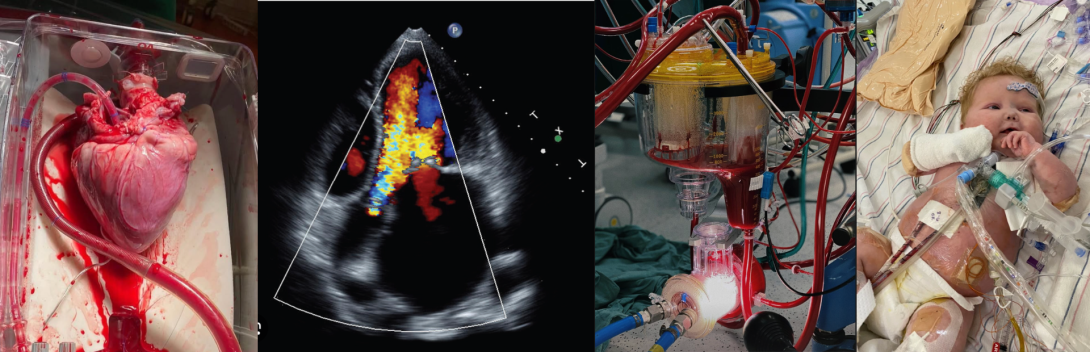

In questi anni in area sanitaria sono andate emergendo nuove professioni sanitarie tra queste il Tecnico di Fisiopatologia Cardiocircolatoria e Perfusione Cardiovascolare si è costituito una nuova identità grazie allo sviluppo di competenze che hanno accompagnato l'evoluzione della cardiologia, della cardiochirurgia e della bioingegneria. Le norme che individuano il profilo professionale del TFCePC sono riconducibili al D.M del 1998. I laureati sono operatori sanitari, con specificità proprie, cui competono la conduzione e manutenzione delle apparecchiature relative alle tecniche di circolazione extracorporea, emodinamica, elettrofisiologia ed ultrasuoni. Le loro mansioni sono prevalentemente di natura tecnica coadiuvando il personale medico. Si tratta, quindi, di una figura professionale nata sulla base di determinate esigenze espresse dal mondo del lavoro all'interno del quale il laureato si inserirà dopo il training di lezioni frontali e tirocini pratici sul campo previsti dal Corso di laurea stesso.